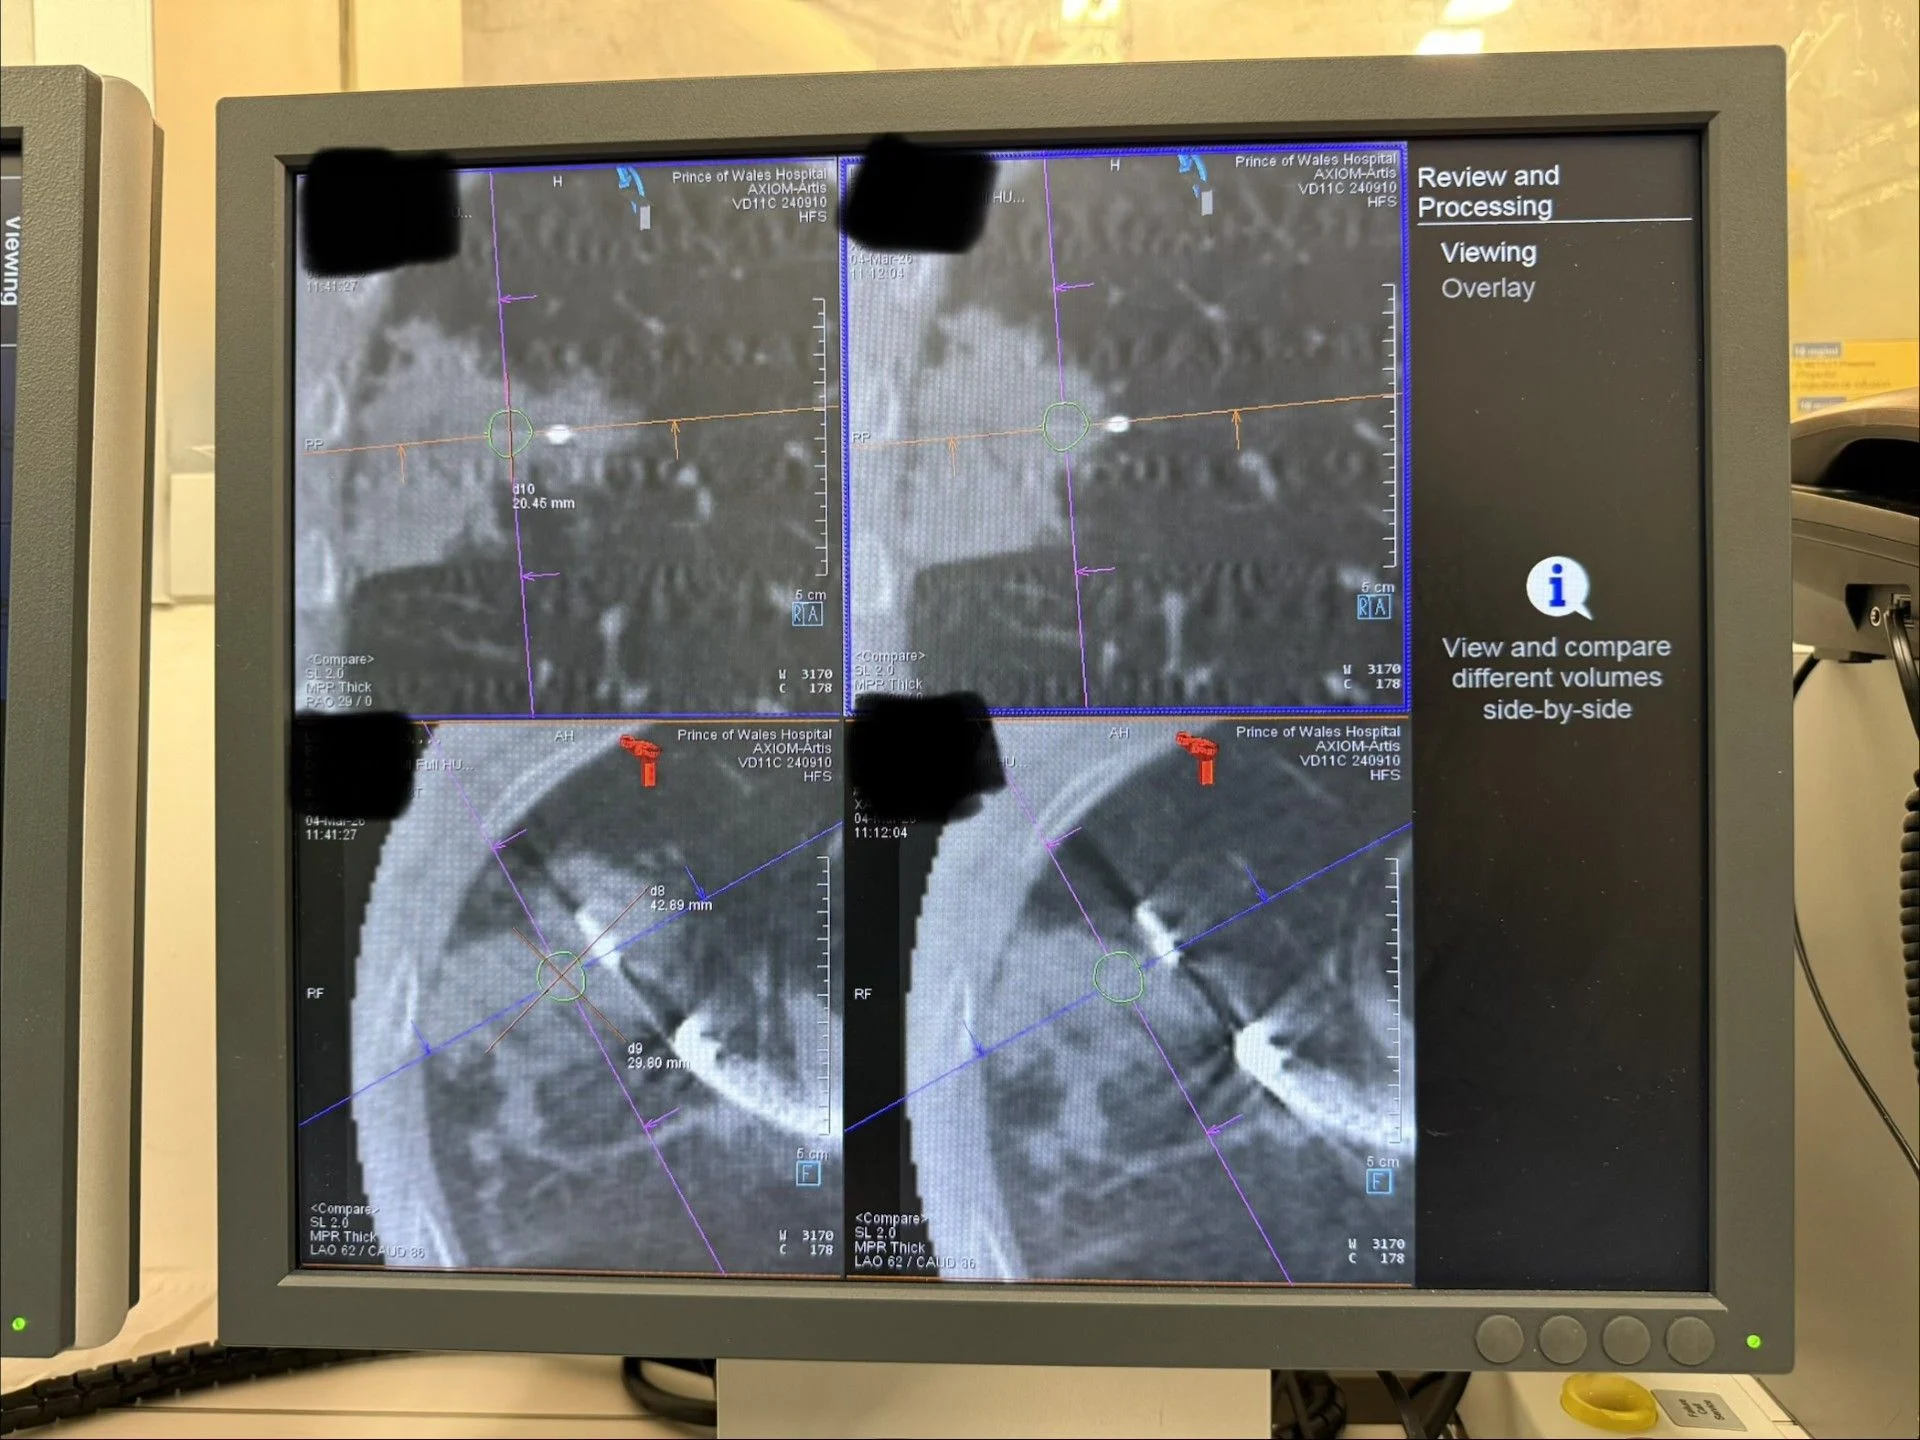

” Hong Kong’s First Cases (First outside Mainland China) Robotic Assisted Bronchoscopy Cryoablation for lung cancer and pulmonary metastases. Cryoablation (at -152 degrees Celsius) has its unique advantages over some other energy modalities, adding to our armamentarium of transbronchial microwave, RFA microperfusion, and PEF.